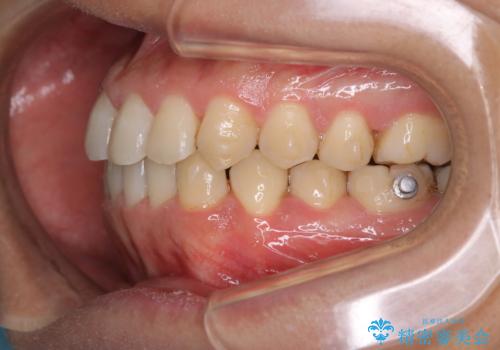

コーヒーを多く飲むインビザライン矯正中の患者様のクリーニング

60分コースでも足りないくらいの着色の量でした。

定期的にクリーニングに来られてますが、かなりの量のコーヒーを飲まれているため着色が多かったです。